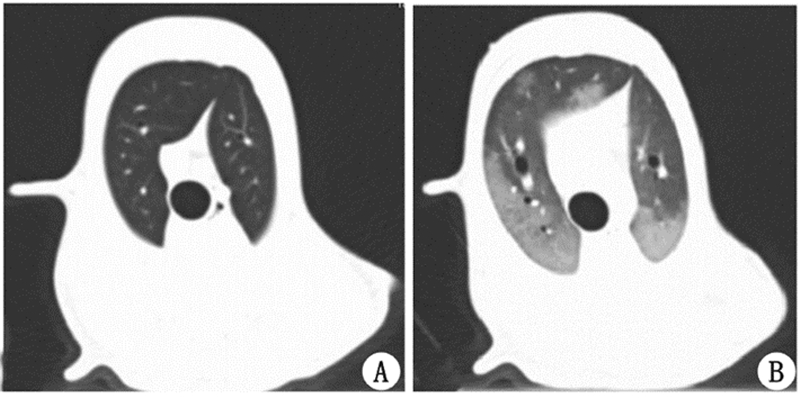

注射油酸后动物模型表现出ARDS的典型影像学特征为:呼气末肺气体容积(FRC)、充气良好及过度充气区比例明显降低,而肺组织密度、肺组织重量、未充气及充气不良肺组织比例明显增加,肺总容积无明显变化,在CT图像上表现为以重力依赖区为主要病变部位,两肺的渗出浸润影,肺组织密度增加,见表 3和图 1。

| A:造模前健康肺影像学表现;B:成模时肺影像学表现,可见两肺的渗出浸润影,肺组织密度增加,以背侧为主 图 1 肺部造模前后典型的影像学特征 Fig.1 Typical imaging presentation of lungs with and without ARDS |

本研究所建立的ARDS动物模型具有以下特征:(1)已知诱因(油酸),急性起病[平均成模时间为(190±58)min];(2)低氧血症,呼气末正压5 cmH2O下 PaO2/FiO2 介于100 mmHg至200 mmHg 之间,PaO2/FiO2均数为166.2 mmHg; (3)如图 1所示典型的ARDS影像学表现[14],以重力依赖区为主要病变部位,两肺的渗出浸润影,肺组织密度增加,通气肺组织减少; (4)呼吸系统及肺顺应性明显降低,前者降低 30.5%而后者降低39%; (5)肺泡水肿,血管外肺水指数从造模前(11.0±1.9)mL/kg升至造模后(25.7±7.9)mL/kg。以上特征表明,本研究所建立的动物模型在疾病起病、氧合[13]、影像学[14]、呼吸力学[15]及血流动力学[16]方面模拟了ARDS的典型特征,为本研究提供了可靠的研究基础。